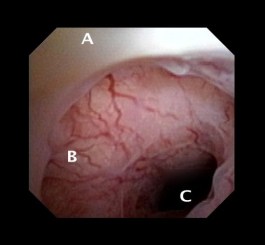

A thorough history will be the most important indication for abnormal uterine bleeding (AUB) associated with a cesarean scar defect (CSD). Along with the history of one or more cesarean sections is a menstrual history indicating a typical bleeding pattern. These women will admit to dark blood, usually old, emanating often several days after a regular menstrual cycle has ceased. Often, the blood is expelled with activity such as exercise or intercourse. These women will report that overall bleeding days associated with their cycle are many, owing to the number of additional days in which there is expulsion of blood from the CSD. In general, this post-menstrual bleeding tends to be also lighter than the regular menstrual flow.